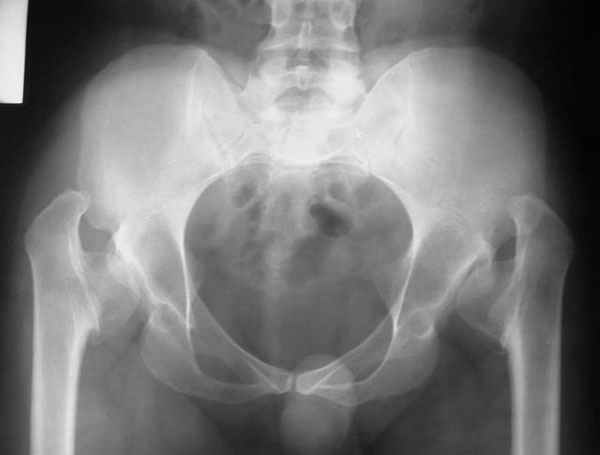

Dear All,This 27 year old presented to a colleague, about 2 years back, with complaints of bilateral hip pain. He was treated symptomatically, but now has increasing pain, and walking distance is being limited.

On examination, he has got a lordotic gait, Trendelenberg negative, bilaterally, hip movements fairly good, with no FFD.X-rays are attached.Kindly give your opinions regarding management and future prognosis.Thanks and regardsMuhammad Amin Chinoy FRCS

It appears that this patient has bilateral congenital hip displasia, as presented on the radiographs. As shown, the problem involves both sides of the hip joint: the acetabulum and proximal femur.

This patient is noted to have a very vertical joint surface orientation, as well, with retroversion of the acetabulum.

In a hip with normal version, (on discussion list) Hip Pain (Dr.Kullerkann) the lines connecting the anterior and posterior acetabular wall as seen on an AP radiograph usually intersect at one point near the superior and lateral portion of the acetabulum. As an example of an abnormal hip, a patient with a retroverted acetabulum will show the figure 8 pattern, with the two shadows crossing over the femoral head. In this particular patient, again it appears that there is a significant amount of retroversion of the acetabular wall, as the anterior wall appears to be more anteriorly displaced than in a normal hip.